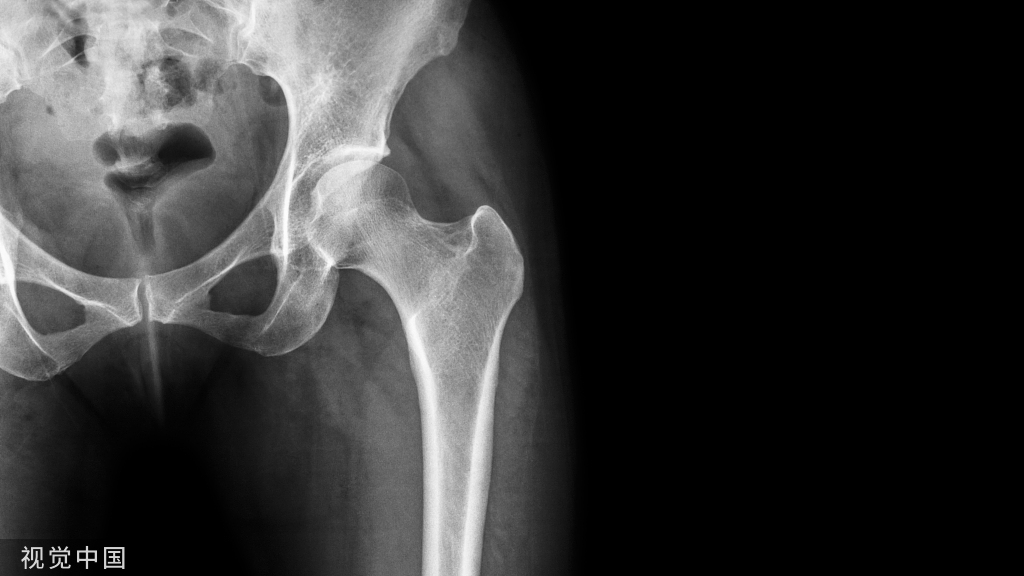

(1)术前常规影像学检查

• 摄正侧位X线片,确定椎间孔形态和大小、髂嵴高度和脊椎形态,确定穿刺部位和方向;

• 摄腰椎过伸过屈动态X线片,判定腰椎稳定性;

• 行腰椎CT和MR检查,观察腰椎问盘突出部位和程度、是否伴有腰椎管狭窄和椎间盘钙化,确定手术方式、工作通道的置入位置与方向。